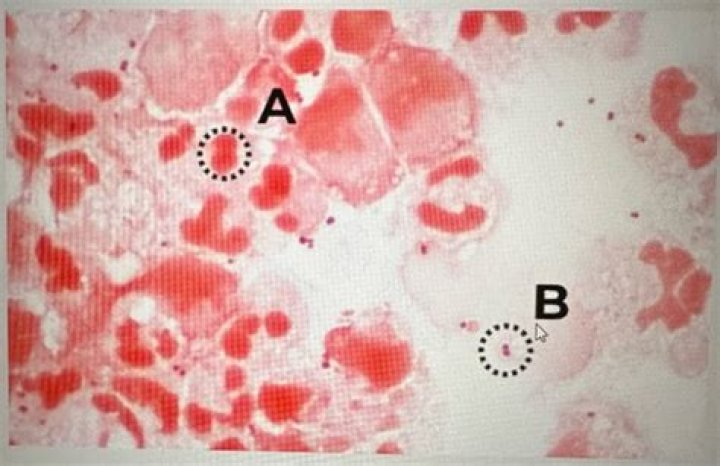

Is eosin a counterstain?

Eosin is the most commonly used counterstain that distinguishes between the cytoplasm and nuclei of cells. It is typically pink, with different shades of pink for different types of connective tissue fibers.